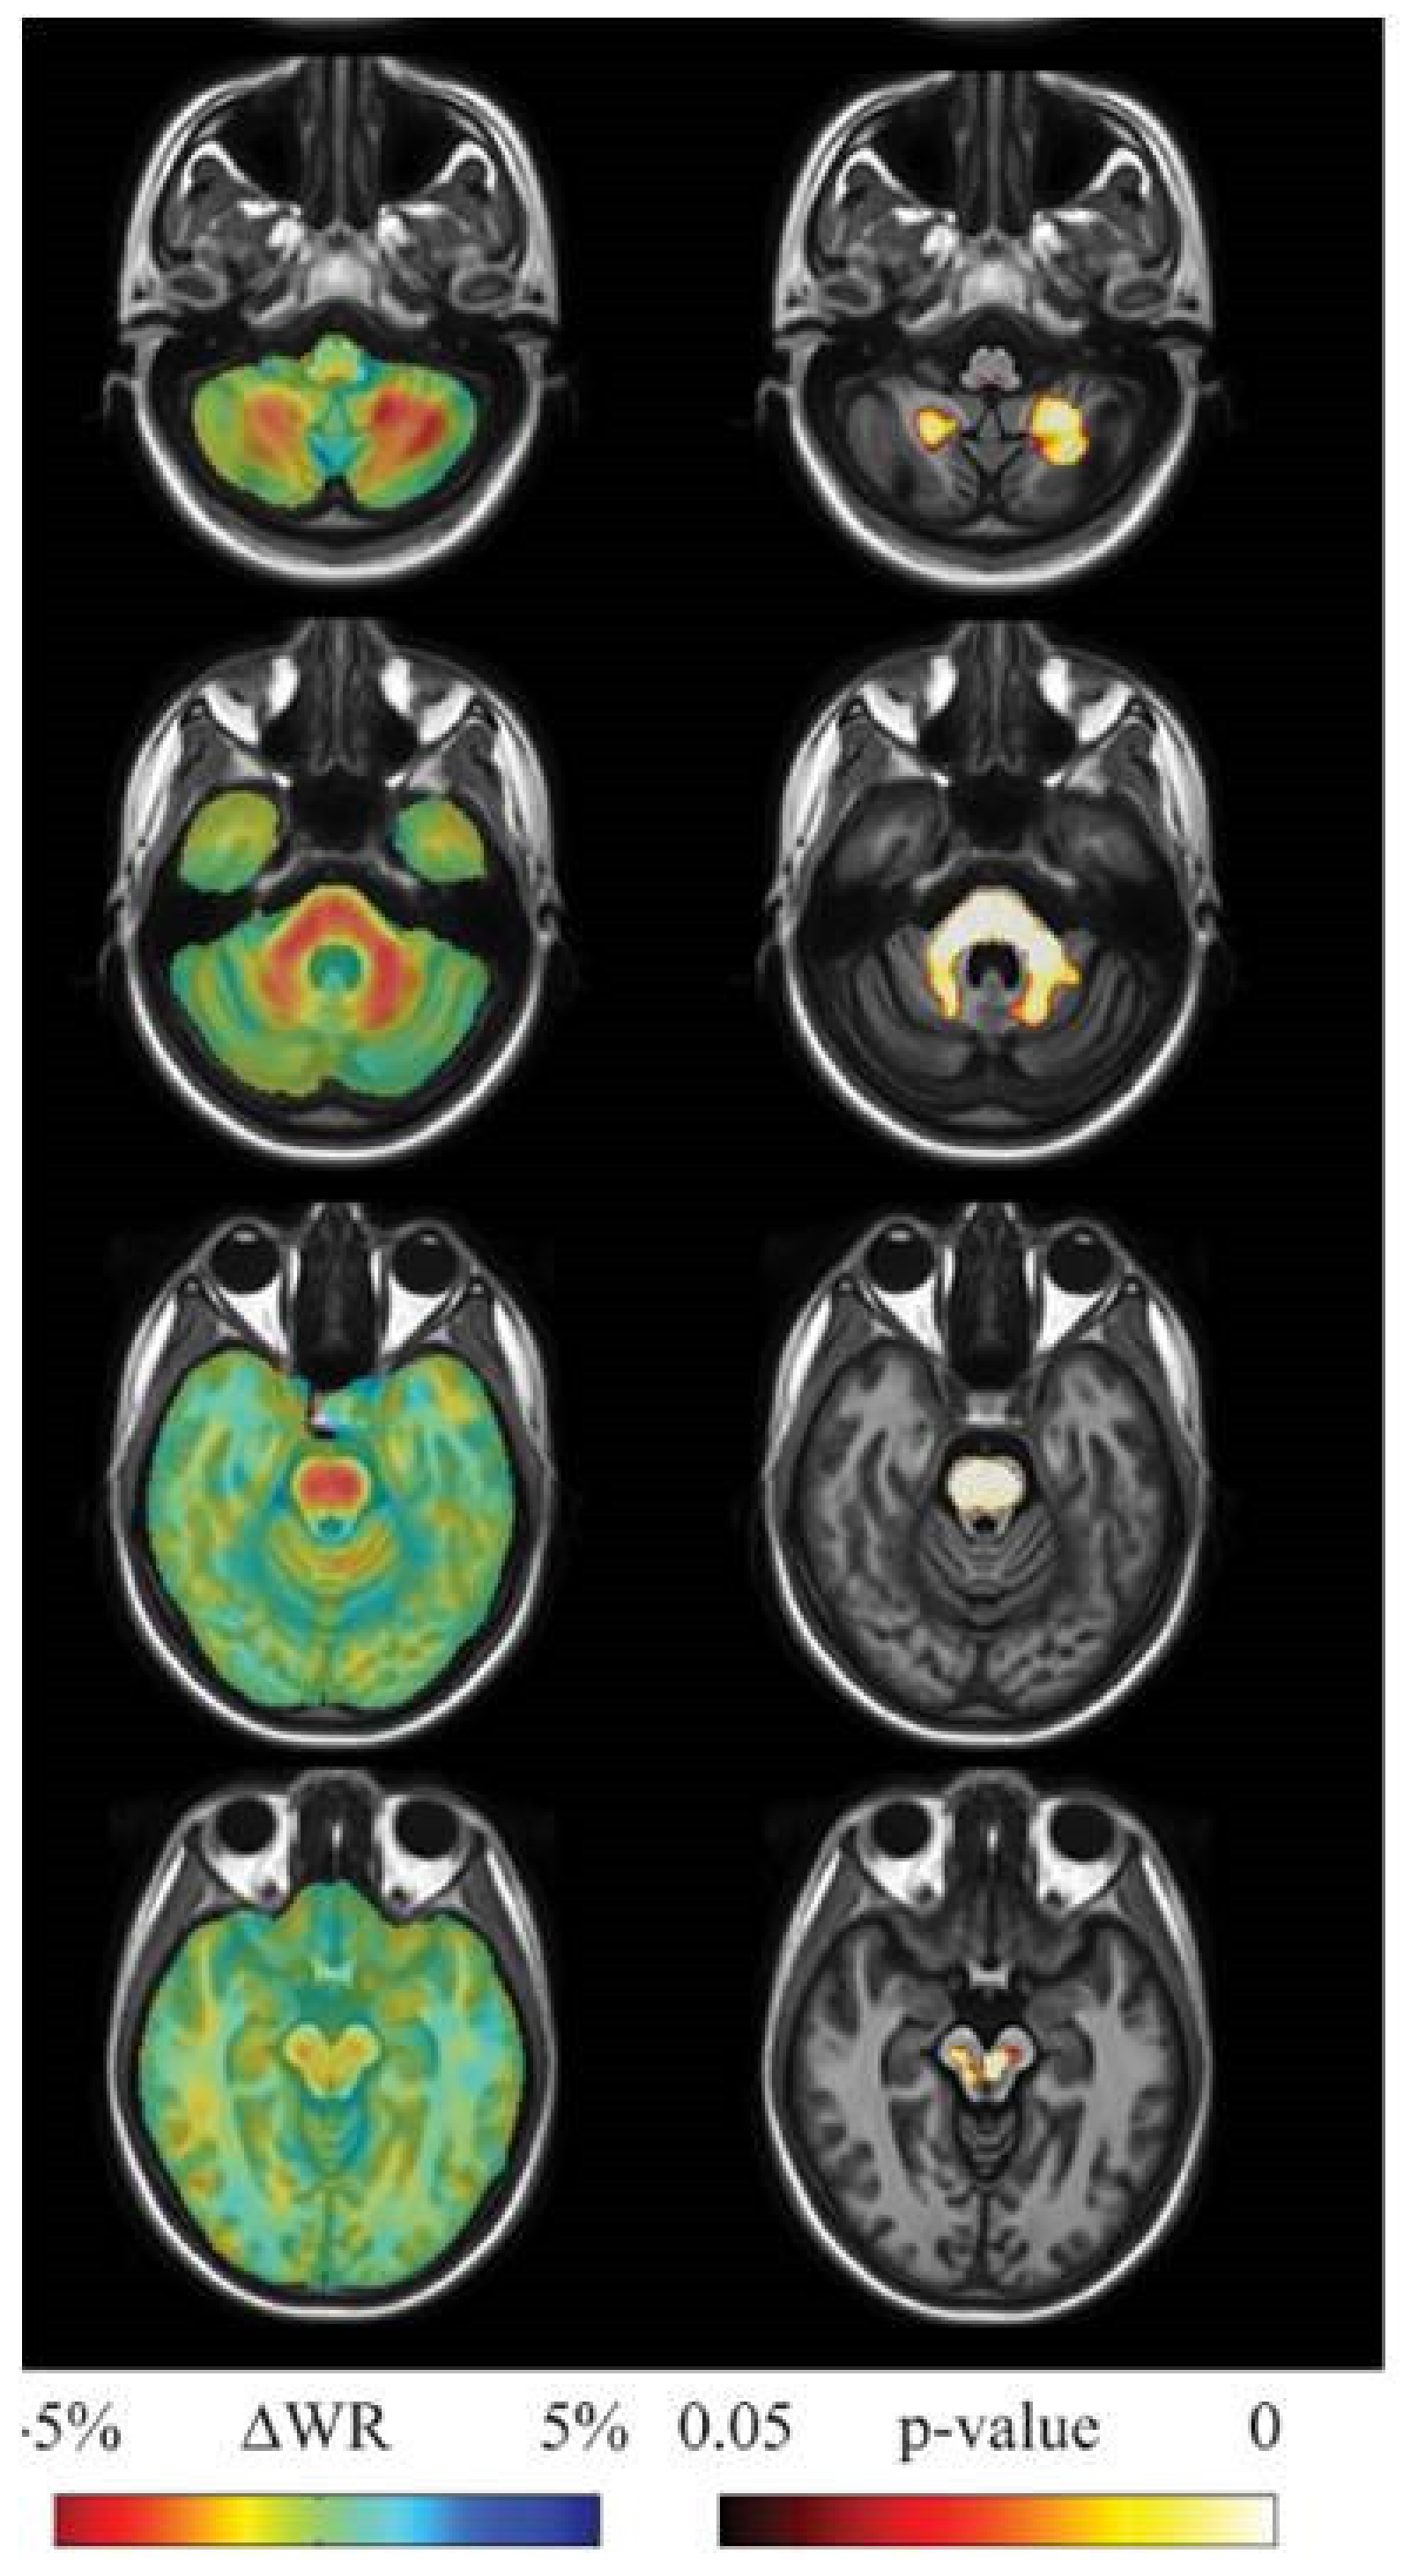

- Adanyeguh, I.M.; Perlbarg, V.; Henry, P.G.; Rinaldi, D.; Petit, E.; Valabregue, R.; Brice, A.; Durr, A.; Mochel, F. Autosomal dominant cerebellar ataxias: Imaging biomarkers with high effect sizes. NeuroImage Clin. 2018, 19, 858–867. [Google Scholar] [CrossRef] [PubMed]